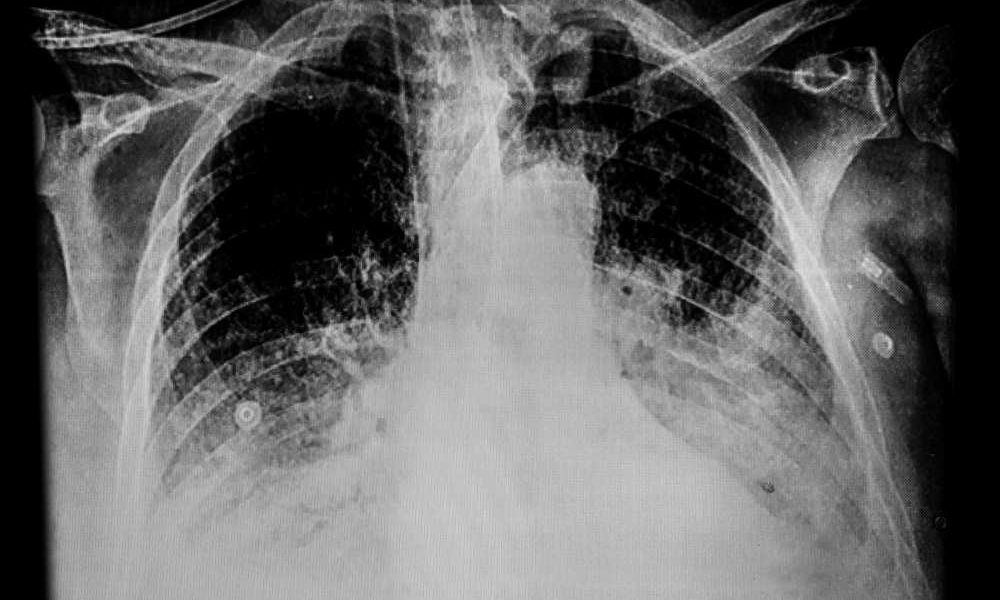

Wśród osób z COVID-19, u których wystąpił udar mózgu, częściej ma on ciężki przebieg – wynika z badania, które publikuje pismo „Stroke”. Ponadto, w grupie z...